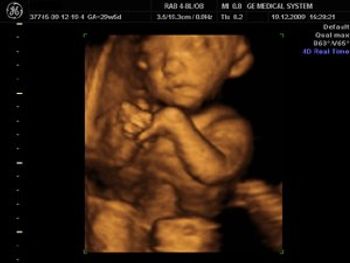

4D image of 29 weeks pregnancy, multiple anomalies: Clinch hand, omphalocoele, single atrium